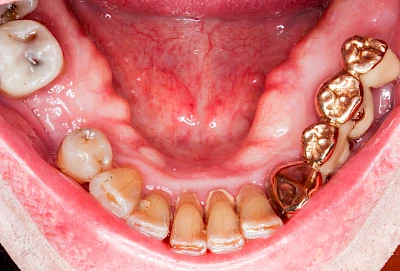

Gehen die Zähne verloren, baut häufig auch der Kieferknochen ab (Knochenschwund). Die Geschwindigkeit und das Ausmaß des Knochenschwundes ist von vielen Faktoren abhängig. Neben der genetischen Veranlagung spielen auch Überbelastungen in Folge, z. B. bei ständigem Knirschen oder Pressen, eine Rolle. Auch wenn Zahnprothesen Tag und Nacht getragen werden, kann die ständige Belastung der Schleimhäute und des Knochens den Knochenschwund beschleunigen.

Aber Achtung: Manche Menschen fühlen sich ohne Zahnprothesen unwohl. Zudem kann es passieren, dass Zahnprothesen (wenn noch eigene Zähne vorhanden sind) nicht mehr passen. Dies gilt vor allem dann, wenn diese Zahnprothesen nicht nur über Nacht, sondern für einen längeren Zeitraum nicht mehr getragen werden.